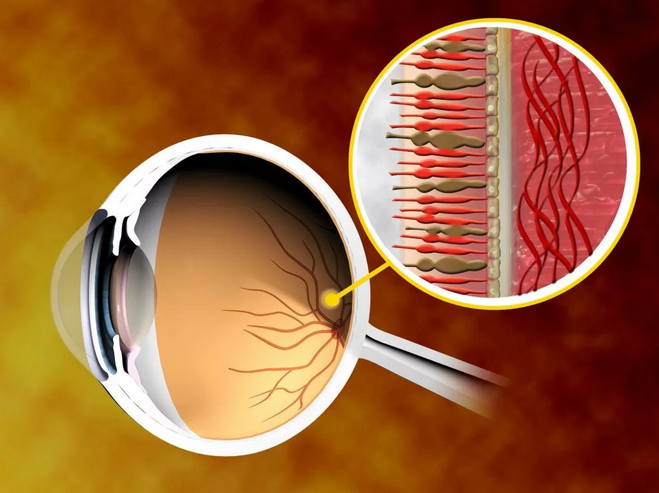

Изображения и анатомия сетчатки глаза

Раздел: Визуальный дайджест